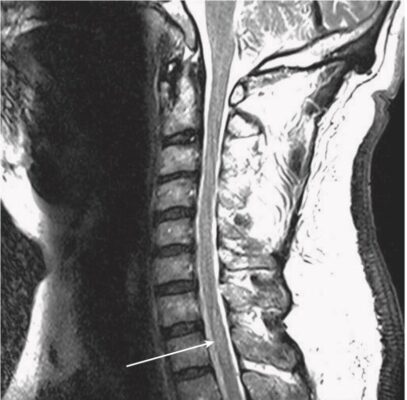

- Thăm dò tốt nhất khi nghi ngờ viêm tuỷ cắt ngang là MRI. MRI không chỉ cho phép nhìn thấy tổn thương mà còn loại trừ các nguyên nhân có thể điều trị được, chẳng hạn như khối u, áp xe và các tổn thương khác gây ra bệnh lý tủy do chèn ép. Chất cản quang có thể được dùng để làm nổi bật các tổn thương, và chụp tủy hiếm khi được xem xét nếu không có MRI.

- Theo một nghiên cứu chụp cộng hưởng từ (MRI), viêm tuỷ cắt ngang cấp tính vô căn thường ảnh hưởng nhất đến vùng tuỷ cổ (60%), tiếp theo là vùng tuỷ ngực (33%).

- MRI cho thấy các đặc điểm giúp phân biệt viêm tuỷ cắt ngang với các bệnh lý như bệnh xơ cứng rải rác.

- Tổn thương ở viêm tuỷ cắt ngang có xu hướng ảnh hưởng đến vùng trung tâm của tủy và liên quan đến hơn 2/3 đường kính của tủy, trong khi ở bệnh xơ cứng rải rác, tổn thương thường ở ngoại vi hơn và liên quan đến ít hơn một nửa đường kính của tủy. viêm tuỷ cắt ngang thường có cường độ tín hiệu cao trên hình ảnh T2W kéo dài theo chiều dọc trên nhiều khoanh tuỷ sống hơn. Số lượng các khoanh đoạn tuỷ bị ảnh hưởng có thể từ 1 hoặc 2 đến 11, và đôi khi ảnh hưởng đến hành tuỷ.

- MRI não có tăng cường tương phản thường được thực hiện để giúp xác định xem các dấu hiệu trên MRI có hướng đến bệnh xơ cứng rải rác chứ không phải viêm tuỷ cắt ngang “vô căn” hay không.

- Trong viêm tuỷ cắt ngang một phần vô căn, một kết quả không cho thấy tổn thương não có nghĩa là khả năng tiến triển bệnh xơ cứng rải rác ở mức 15% đến 44%. Khi thấy các tổn thương não như mảng chất trắng (đặc biệt là quanh não thất), nguy cơ phát triển bệnh xơ cứng rải rác tăng lên từ 44% đến 93%.